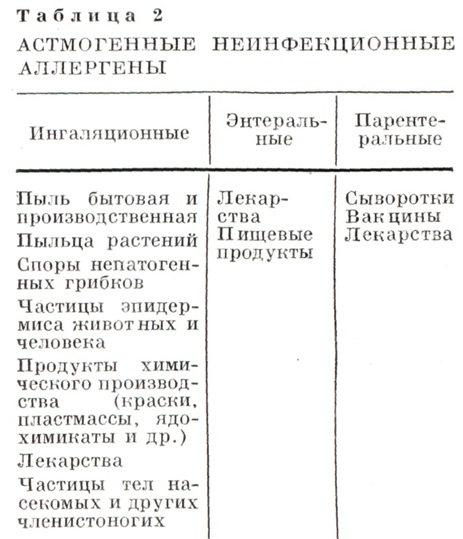

В Советском Союзе вопрос классификации Б. а. обсуждается с 1963 г. В наст, время принята и вводится в практику классификация основных этиологических форм и стадий болезни, предложенная А. Д. А до и П. К. Булатовым (табл. 1). Согласно классификации различают две основные формы Б. а.— инфекционно-аллергическую и неинфекционно-аллергическую (атопическую). Первая связана с сенсибилизацией бактериальными аллергенами, к-рые поступают из очагов хрон. инфекции, локализованных преимущественно в респираторном аппарате. Вторая форма относится к группе наследственно обусловленных аллергических заболеваний (см. Атопия) и вызывается неинфекционными аллергенами.